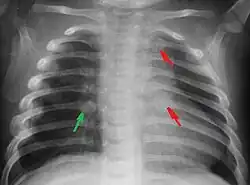

Most nations with child abuse laws deem the deliberate infliction of serious injuries, or actions that place the child at obvious risk of serious injury or death, to be illegal.[36] Bruises, scratches, burns, broken bones, lacerations—as well as repeated "mishaps", and rough treatment that could cause physical injuries—can be physical abuse.[37] Multiple injuries or fractures at different stages of healing can raise suspicion of abuse.

C. Henry Kempe and his colleagues were the first to describe the battered-child syndrome in 1962.[40] The battered-child syndrome is a term used to describe a collection of injuries that young children sustain as a result of repeated physical abuse or neglect.[41][42] These symptoms may include: fractures of bones, multiple soft tissue injuries, subdural hematoma (bleeding in the brain), malnutrition, and poor skin hygiene.[42][43]

The immediate physical effects of abuse or neglect can be relatively minor (bruises or cuts) or severe (broken bones, hemorrhage, death). Certain injuries, such as rib fractures or femoral fractures in infants that are not yet walking, may increase suspicion of child physical abuse, although such injuries are only seen in a fraction of children suffering physical abuse.[90][91] Cigarette burns or scald injuries may also prompt evaluation for child physical abuse.[92]

Investigation

Suspicion for physical abuse is recommended when injuries occur in a child who is not yet able to walk independently.[162] Additionally, having multiple injuries that are in different stages of healing and having injuries in unusual location, such as the torso, ears, face, or neck, may prompt evaluation for child abuse.[162] Medical professionals may also become suspicious of child abuse when a caregiver is not able to provide an explanation for an injury that is consistent with the type or severity of the injury.[163]